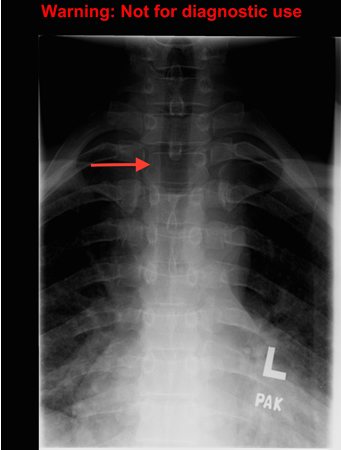

Spine radiograph: the "winking owl" sign (asymmetrical appearance caused by destruction of the pedicle)

The "winking owl" sign (arrow): asymmetric appearance of spine on plain radiographs caused by destruction of the pedicle